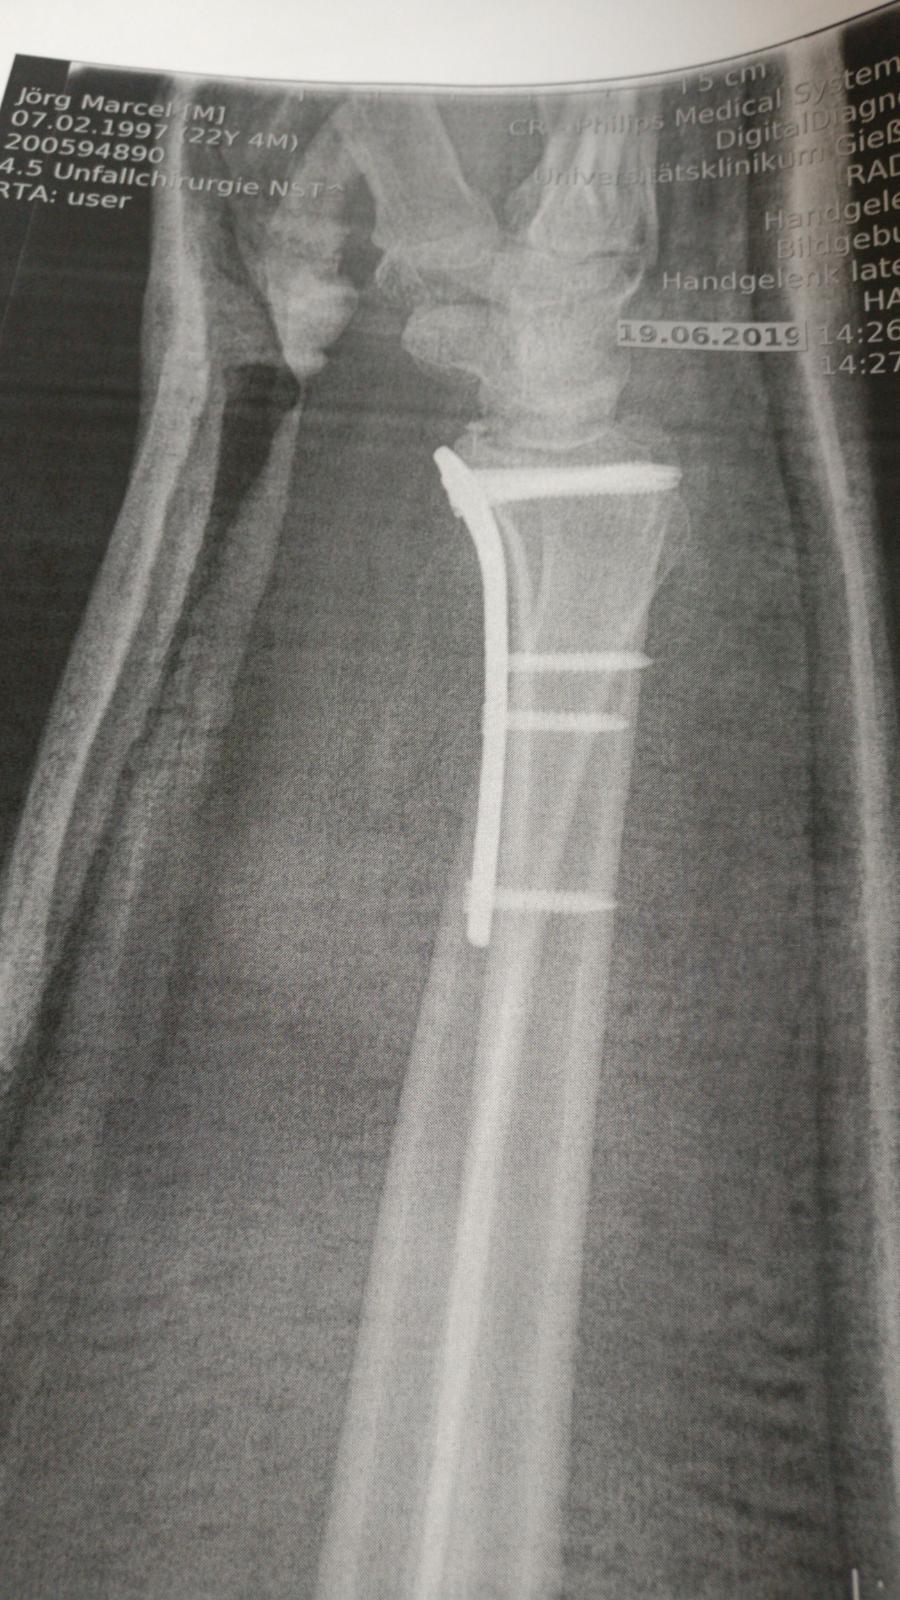

Got to leave the Hospital today. Surgery was on tuesday instead of monday

On the positive you got some nice new titanium hardware! Quick heals and good feels being sent your way brother.